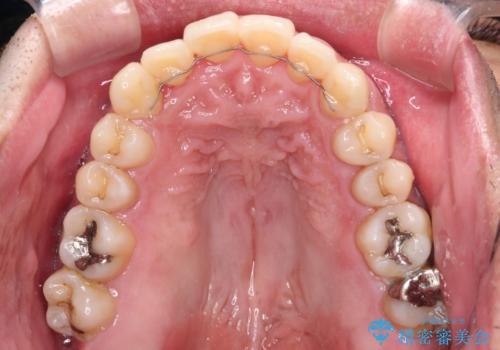

インビザラインは1日22時間を目標にマウスピースを装着することで歯列を改善するものです。

そのため、上下の歯が接触することはほとんどなく、マウスピースを介した咬合において歯列矯正が進んでいきます。

この方は元々骨格的な偏位が大きかったためか、治療中に下顎骨が上顎骨よりも右外側に誘導されて、右側の奥歯が全く咬合しない状態が続いてしまいました。

最終的にはゴムかけなどを活用して改善することができましたが、4年近い治療期間を要することとなりました。